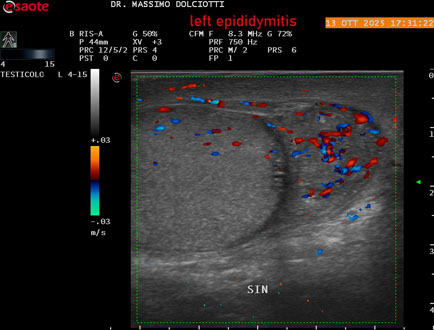

Data inserimento: 14/10/2025

Ecografia del: 13/10/2025

Strumento: Esaote MyLab Eight

Sonda: Lineare Multifrequenza 4-15 MHz

Età Paziente: M 70 anni

Motivazione dell'esame: da 2 giorni dolore al testicolo sinistro.

Commento all'esame: le immagini ed il video documentano l'epididimo sinistro spiccatamente aumentato di volume e di vascolarizzazione, come da flogosi. Didimo sinistro lievemente aumentato di volume. Quadro clinico ed ecografico da ricondurre ad epididimite acuta sinistra.

Conclusioni: epididimite acuta sinistra (acute left epididymitis).

Presentazione: Dr. Massimo Dolciotti - Ancona